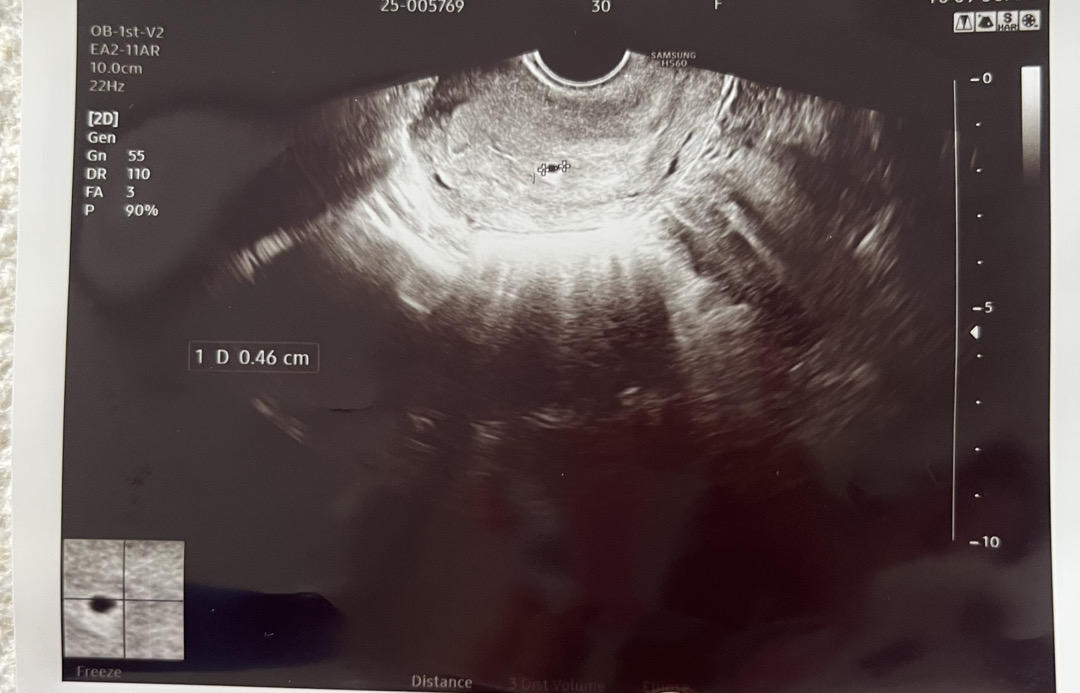

아기집💗

어제 난생처음으로 2줄보고 산부인과 가서 아기집 보고왔어요 🥹 4주 반 정도되었다고 하시는데, 크기가 이정도면 괜찮은거겠죠?? 병원 또 가서 보고싶은데 연휴라 가지를 못하고있어용 ㅠ